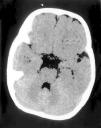

Las exploraciones complementarias realizadas fueron normales: hemograma, bioquímica sérica elemental, creatinfosfocinasa, ácido láctico, piruvato, aminoácidos en suero, ácidos orgánicos en orina, ácidos grasos libres en plasma, carnitina sérica total, carnitina libre, acilcarnitina, cociente acil/libre, equilibrio acidobásico, amonio, hormonas tiroideas, cariotipo, citoquímica de líquido cefalorraquídeo, electromiograma y velocidad de conducción motora de nervio peroneo, biopsia de músculo con estudio estructural, histoquímico y de cuantificación de enzimas de la cadena respiratoria mitocondrial, estudio del ADN mitocondrial de músculo en búsqueda de las mutaciones T8993G, T8993C y A9176C, deleciones únicas o múltiples y depleción por Southern blot, test de edrofonio, estudio de potenciales evocados auditivos del tronco cerebral y una tomografía computarizada (TC) craneal (fig. 1). Se realizaron tres estudios de resonancia magnética (RM) craneal a los 7, 9 y 15 meses de vida que mostraron alteración en la intensidad de la señal en tegmento mesencefálico, pontino y bulbar, más marcado en regiones dorsales (figs. 2 y 3).

Figura 2.RM craneal: secuencia ponderada en T2 a nivel del polígono. Hiperintensidad de la señal del tegmento paramediano y sustancia gris periacueductal.